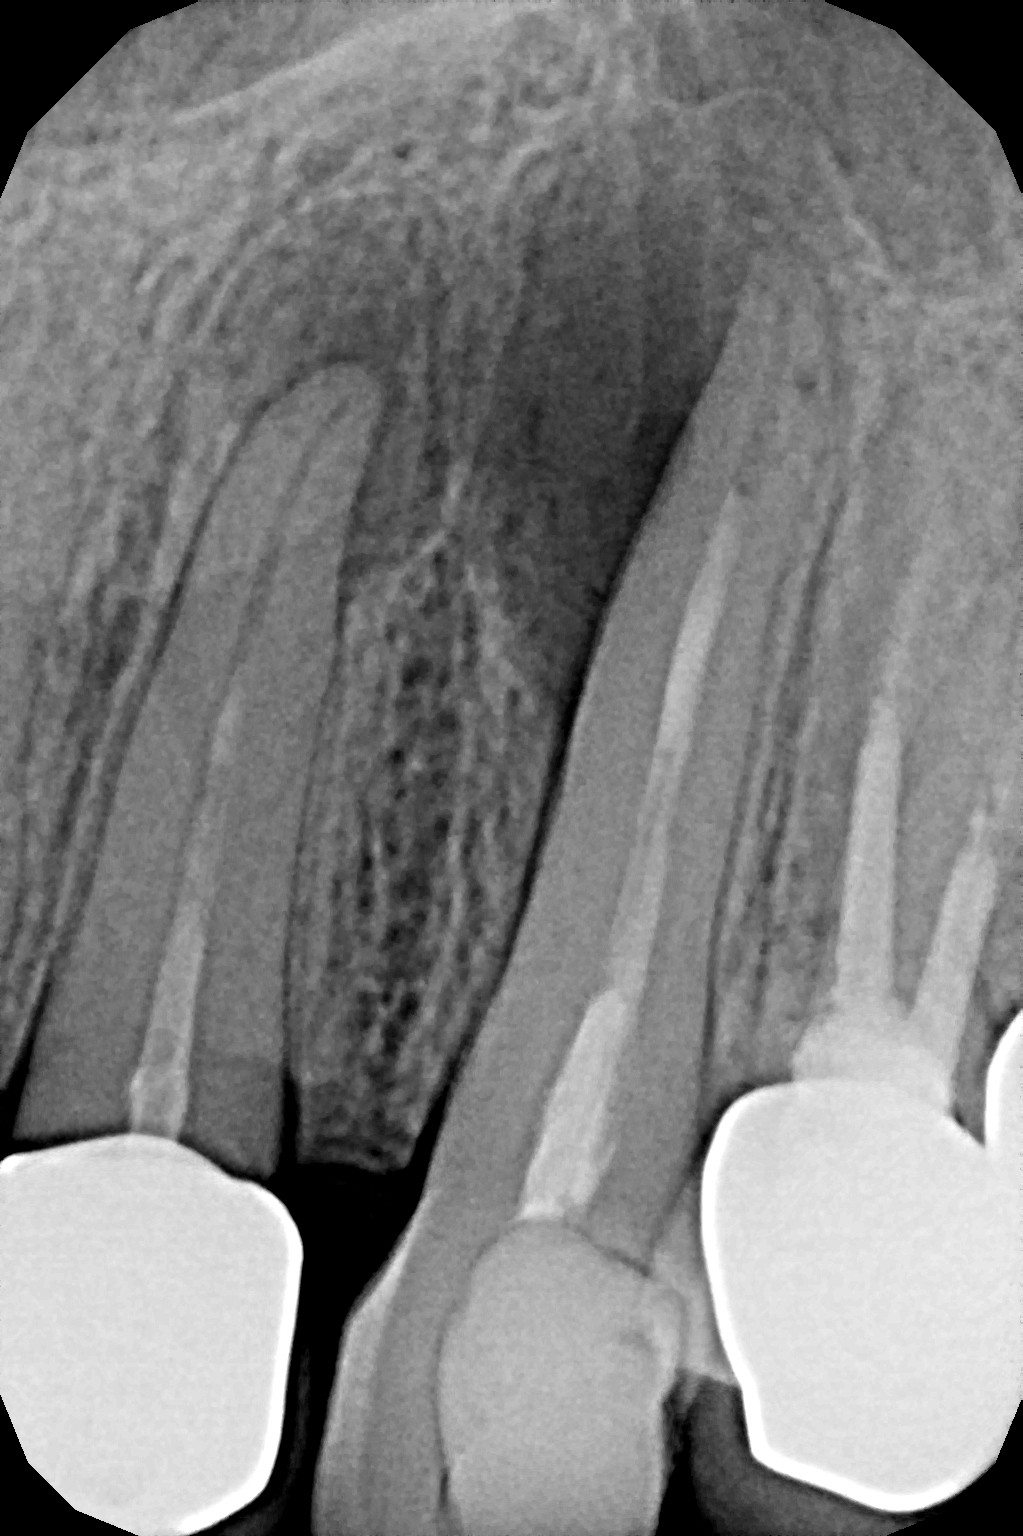

Najczęstsze przyczyny utrudnień lub niepowodzenia leczenia to pozostawione w kanałach zębów złamane narzędzia endodontyczne po uprzednim leczeniu, obliteracja, czyli bardzo słaba drożność kanałów korzeniowych lub wręcz jej brak, do której dochodzi na skutek przewlekłych stanów zapalnych miazgi, czy wreszcie niestandardowa anatomia zęba.

Leczenie kanałowe zęba pod mikroskopem daje lepszy wgląd w pole zabiegowe podczas odnajdywania i udrażniania kanałów korzeniowych oraz ich poszerzania i precyzyjnego wypełniania. Powiększony obraz ułatwia i przyspiesza pracę szczególnie przy niestandardowej anatomii zęba.

Konieczność powtórnego leczenia endodontycznego może zaistnieć w sytuacji, gdy kanały zęba nie zostały wypełnione do ich anatomicznego wierzchołka lub w trakcie leczenia doszło do złamania i pozostawienia ułamanego narzędzia w świetle kanału korzeniowego. O konieczności powtórnego leczenia endodontycznego może również zadecydować zmiana zapalna przy wierzchołku korzenia, która jest widoczna jedynie na obrazie kontrolnego zdjęcia rtg.